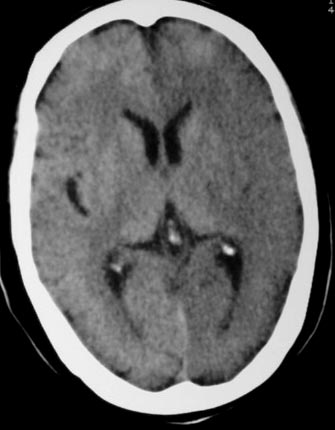

失语及右侧肢体无力3小时

左侧大脑半球与对侧相比较密度普遍密度降低,结合临床首先考虑是脑梗塞早期,必要时复查或mri。

左侧脑表面脑变窄,左外侧裂池受压变窄。

左侧大脑半球密度减低,左外侧裂消失。脑梗塞急性期

左侧侧裂池消失,脑沟变浅.典型的一侧大脑半球缺血改变.可以诊断:左侧大面积脑梗塞.

左侧大脑半球密度普遍降低,脑沟池消失,考虑大面积梗塞

左侧大脑半球大片密度减低影,脑沟变浅,外侧裂变窄,中线结构无明显移位。左侧大面积脑梗塞,大脑中动脉堵塞所致,愈后不好呀!应早期溶栓啊。

典型的左侧大脑半球早期缺血性脑梗塞(符合大脑前动脉、中动脉、大脑后动脉供血区。)

左侧颞顶叶皮层与白质呈大片状低密度影,左侧脑室颞角,及侧裂池受压变小.中线居中.

意见:左侧颞顶叶大面积梗塞(脑膜中动脉梗塞),

典型的左侧大脑半球缺血性脑梗塞早期表现[左侧大脑半球皮质密度减低与脑白质密度一致(脑皮质征),左侧豆状核轮廓模糊,密度与脑白质一致(豆状核征),结合临床有失语及右侧肢体无力3小时]。